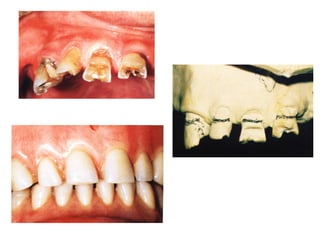

Definition

The overdenture is a complete or partial denture

prosthesis constructed over existing teeth, root

structure and/or dental implants.

 The overdenture is also called “overlay denture”,

“overlay prosthesis”, “superimposed prosthesis”